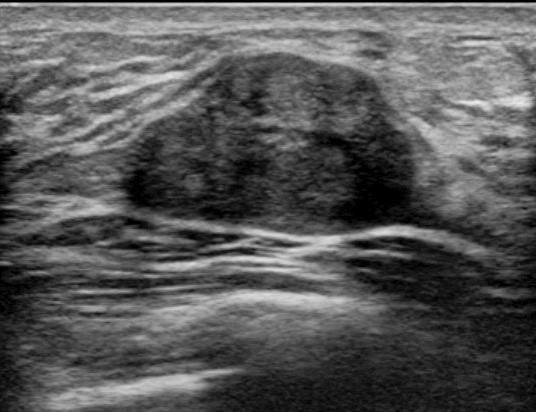

VAB超音波写真

乳腺診療には超音波検査が重要です。しこり、痛みなど乳腺の異常がある場合には診察と乳腺超音波検査を行い、実際にしこり(腫瘍など)があるかどうかを判断します。当クリニックでは富士フイルムヘルスケア社の超音波診断装置を使用しており、高周波プローブによって乳腺の繊細な画像検査が可能です。またリアルタイムエラストグラフィという機能でしこりの硬さを推定することができ、より正確な診断に役立ちます。

超音波検査で観察したしこりが乳がんを疑わず、良性疾患の可能性が高い場合には定期的な超音波検査による経過観察を行います。一方、しこりに悪性の可能性がある場合にはまず穿刺吸引細胞診(FNA:fine needle aspiration)を行います。これは注射に用いる針よりも細い針で乳腺のしこりなどから細胞を吸引し、顕微鏡で診断する検査です。この結果、悪性と判断されれば更なる精密検査を行い、乳がんに対する治療計画を立てていきます。FNAでも良悪性の判定が困難な場合や早期の乳がんが疑われ、ある一定量の組織採取が必要な場合には乳腺針生検を行います。当院ではより正確な診断をおこなうために、吸引をかけて組織を確保しながら針生検を行うVAB(vacuum-assisted breast biopsy)を行っています。FNAもVABも超音波検査で針の方向を確認しながら行います。